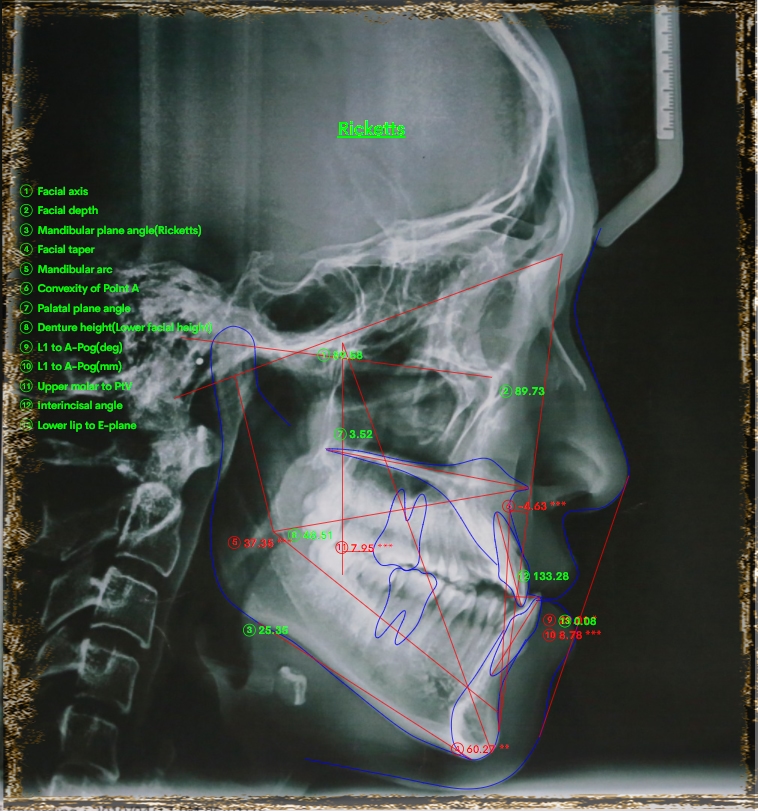

Phân tích phim cho thấy sai hình xương loại III

Chồng phim trước và sau điều trị